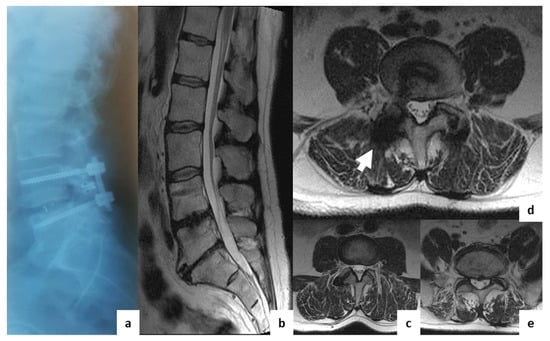

Comparison of MRI Visualization Following Minimally Invasive and Open TLIF: A Retrospective Single-Center Study

3. Results